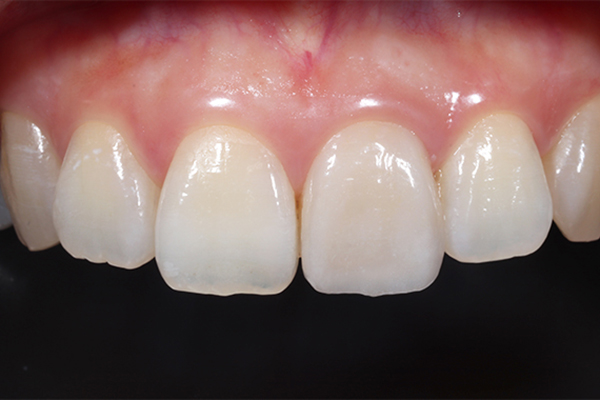

咬合再構成も含めた審美的な補綴治療を学べます。